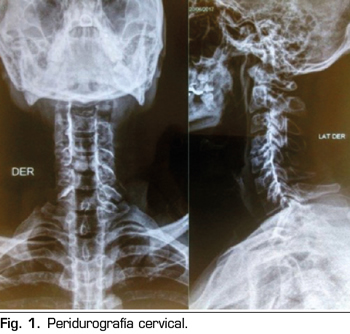

Pasa a recuperación donde hubo regresión completa del bloqueo cervical; el paciente se mantiene estable y con evolución favorable; fue evaluado por el servicio de terapia del dolor, donde se decide observar la permeabilidad del catéter, utilizando una sustancia de contraste iodado no iónico 3 cc, evidenciando en la imagen de “Peridurografía cervical” la difusión del contraste a ambos lados del espacio epidural (Figura 1), procediendo a continuar la analgesia en el postoperatorio a través del catéter epidural cervical con morfina 5 mg, bupivacaína 0,05 % y cloruro de sodio a 0,9 % 90 cc a través de bomba elastómerica a un flujo de 0,5 cc/hora durante 5 días. Se realizó el seguimiento durante la hospitalización, con controles en el postoperatorio inmediato y al primer día, teniendo un EVA 0/10, en estas dos evaluaciones, sin presentar ninguna complicación; fue dado de alta el 2.º día del postoperatorio con la infusión por bomba elastómerica, con un EVA 0/10, reevaluándose al 5.º día del postoperatorio por consultorio externo de terapia del dolor, presentando un EVA 0/10 y sin complicaciones desde el alta (Figura 2), procediendo al retiro del catéter epidural.